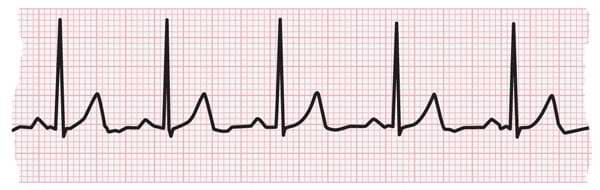

Jun 14, 17 · Sinus tachycardia is recognized on an ECG with a normal upright P wave in lead II preceding every QRS complex, indicating that the pacemaker is coming from the sinus node and not elsewhere in theMay 05, 15 · A 'supraventricular tachycardia' is a rapid heart rate that originates from above or within the atrioventricular (AV) node It is a blanket term that includes a lot of different rhythms and is simply a starting point on the road to diagnosisAug 01, · The middle strip shows adenosine acting on the AV node to suppress AV conduction — there are several broad complex beats which may be aberrantlyconducted supraventricular impulses or ventricular escape beats (this is extremely common during administration of adenosine for AVNRT)

Rhythm analysis indicates sinus tachycardia at over 100 bpm First degree heart block is also present This encounter shows a fast rate over 100 bpm, with a regular rhythm and P waves, indicating sinus tachycardia The extremely long delay between the P wave and QRS indicates first degree heart blockThis EKG practice test is designed to help you learn to recoginze all of the EKG rhythms that you will encounter during emergencies and during the AHA ACLS provider course Use these EKG practice tests to help you become proficient in your rapid rhythm identificationCompeting sinus and idioventricular pacemakers are present There is underlying sinus arrhythmia, with sinus capture occurring when the sinus rate exceeds the idioventricular rate This patient was a healthy 36year old marathon runner with presumably very high resting vagal tone causing sinus bradycardia and sinus arrhythmia

Answer A Explanation Both the atrial and ventricular rates are between 60 and 100 bpm in normal sinus rhythm 11) Identify a rhythm using these criteria regular rhythm, ventricular and atrial rates are 74 beats/minute, P wave precedes each QRS, PR interval and QRS duration within normal limits A) Sinus bradycardiaNov 23, 19 · Sinus tachycardia refers to an increased heart rate that exceeds 100 beats per minute (bpm) The sinus node, or sinoatrial node, is a bundle ofACLS Rhythms for the ACLS Algorithms 257 5 Sinus Tachycardia Defining Criteria and ECG Features Rate >100 beats/min Rhythm sinus PR ≤0 sec QRS complex normal Clinical Manifestations None specific for the tachycardia Symptoms may be present due to the cause of the tachycardia (fever, hypovolemia, etc) Common Etiologies Normal exercise

Sinus Tachycardia Sinus tachycardia is sinus rhythm with a rate of > 100bpm Sinus tachycardia is an example of a supraventricular rhythm In sinus tachycardia the sinus node fires between 100 and 180 beats per minute, faster than normal The maximal heart rate decreases with age from around 0 bpm to 140 bpmSinus tachycardia is the most common tachyarrhythmia (tachycardia) Sinus tachycardia is the result of an increased rate of depolarization (ie increased automaticity) in the sinoatrial node This simply means that the sinoatrial node discharges electrical impulses at a